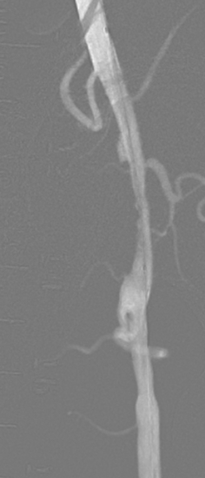

冲击波治疗前后管腔获得情况

术前造影

术后造影